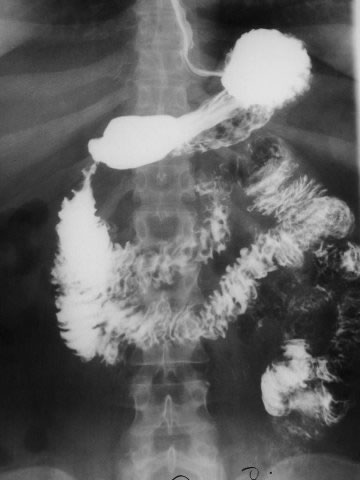

gsg/giardiasis1.jpg